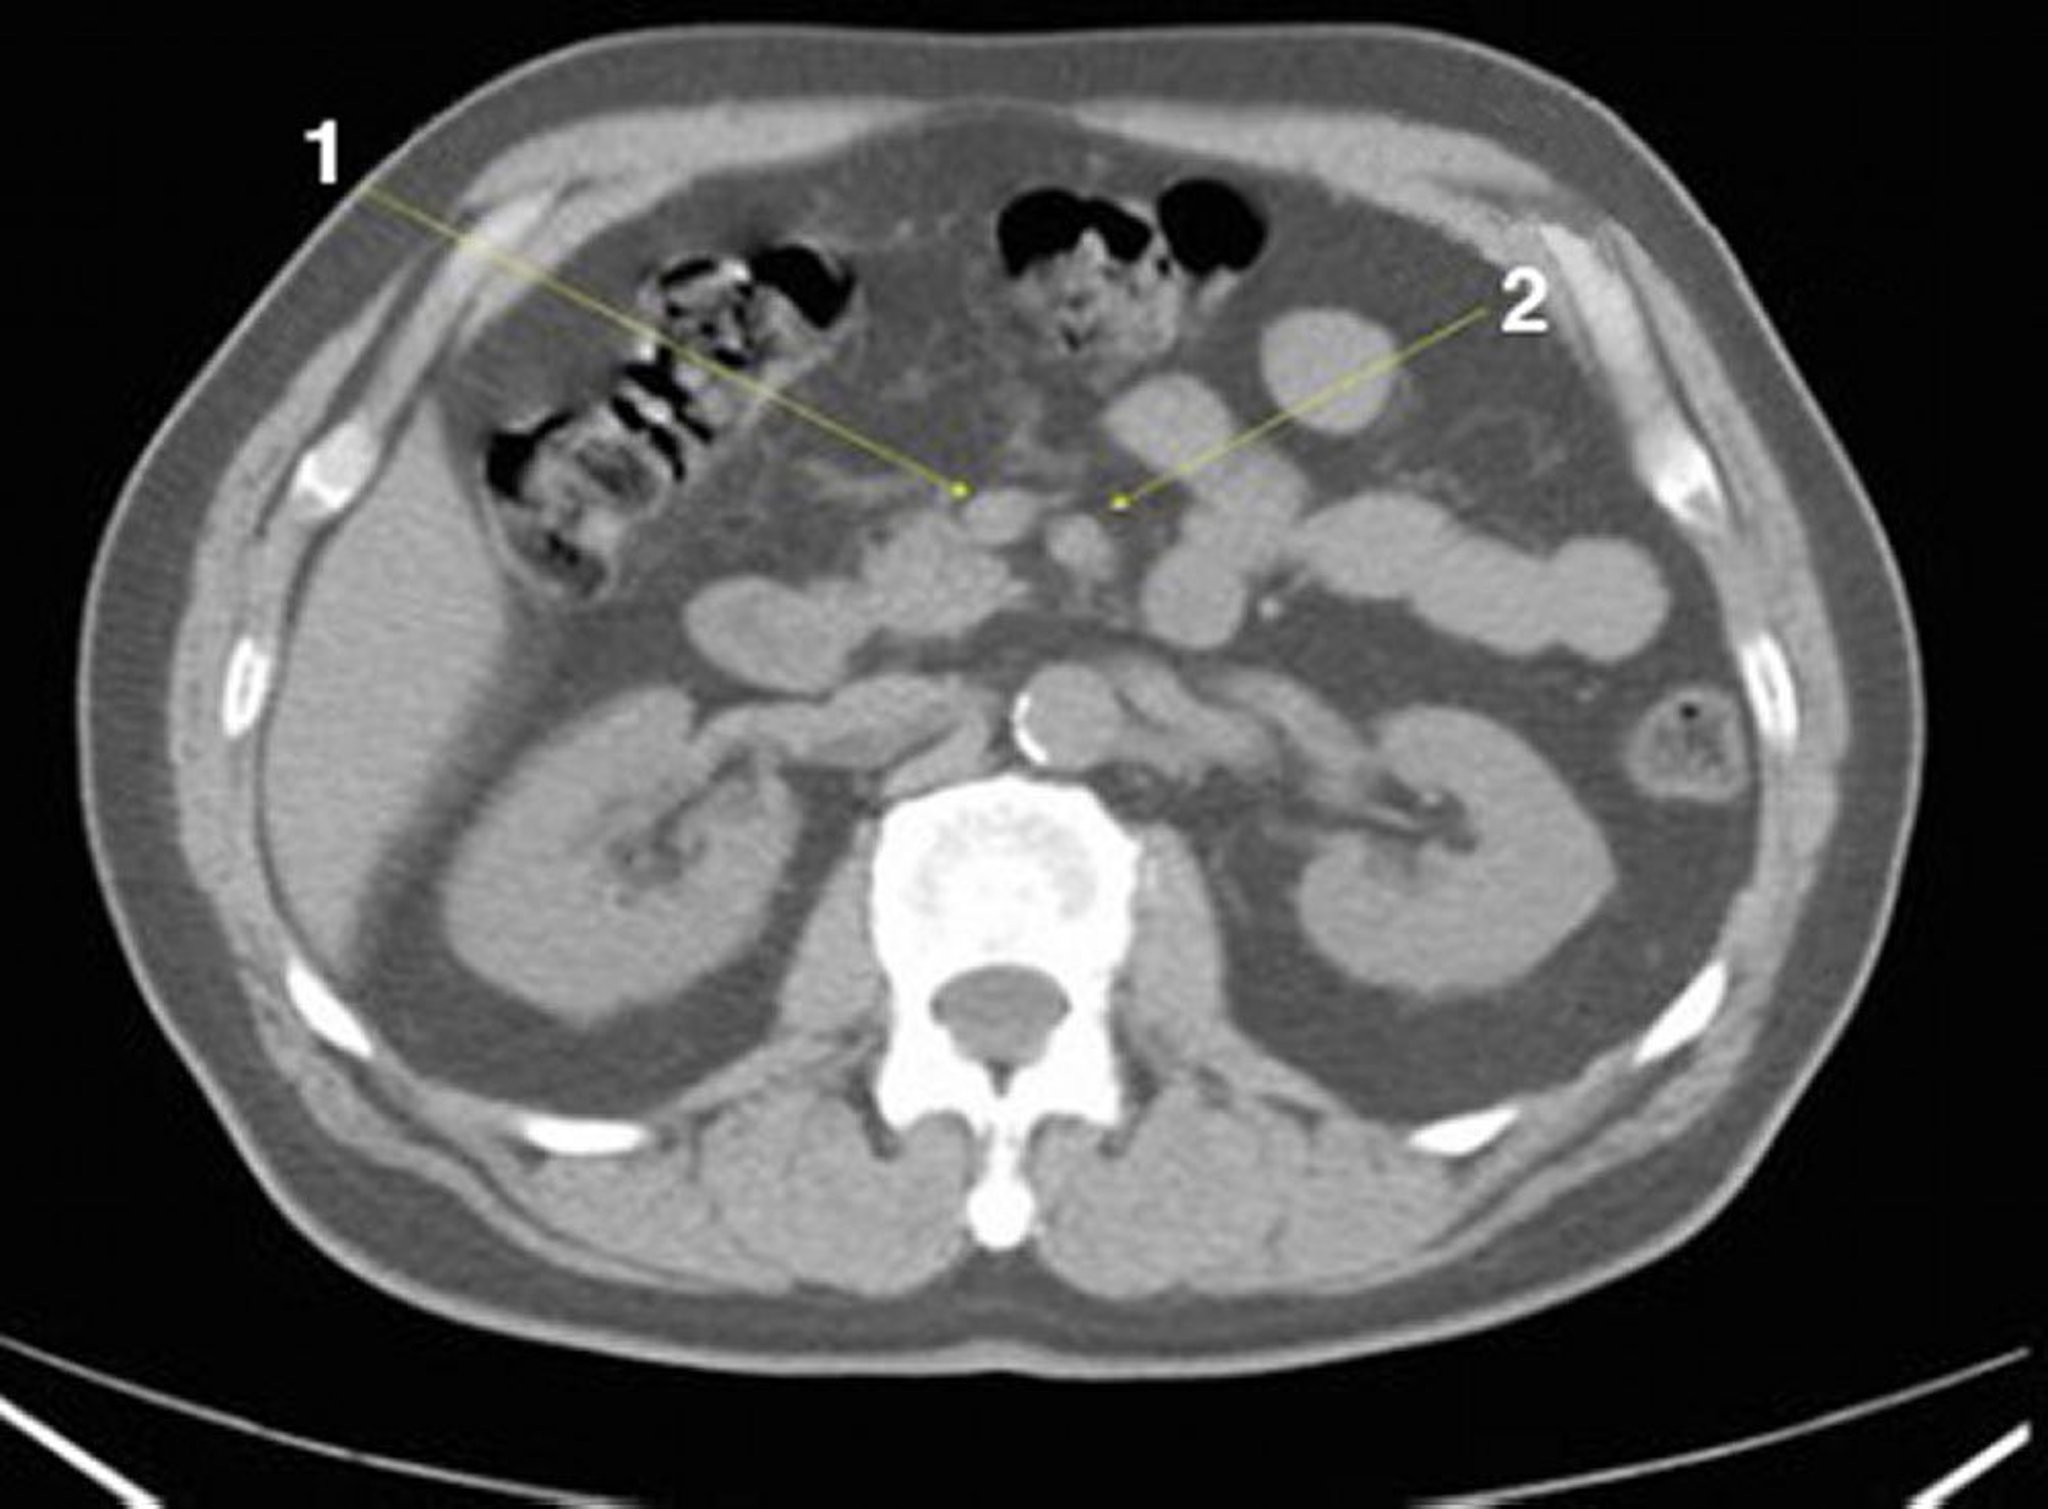

TC senza contrasto dell'addome e della pelvi che mostra un'anatomia normale (Slide 13)

1 = vena mesenterica superiore; 2 = arteria mesenterica superiore.